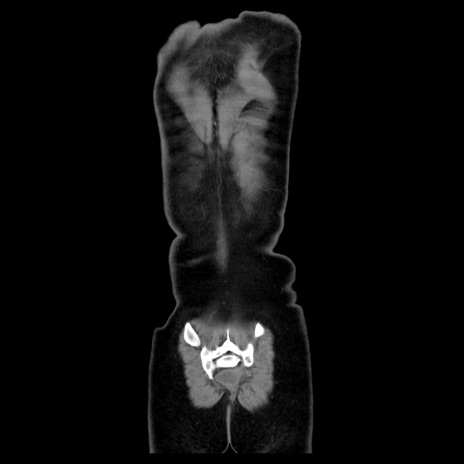

MRI(4日後)